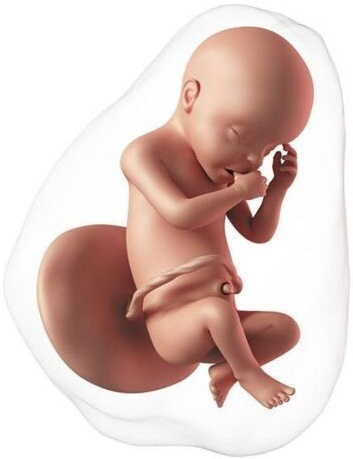

Cada vez se parece más a un bebé. Mide aproximadamente 11 a 12 cm y pesa unos 80 gramos. La proporción cabeza-cuerpo se acerca más a la que tendrá después del nacimiento, las orejas y los ojos están casi en su posición final. Los brazos y las piernas se alargan. La conexión entre el cerebro y los músculos madura, el bebé empieza a realizar movimientos coordinados. Puede mover los ojos, tragar, abrir y cerrar las manos, flexionar las extremidades y también puede coger con las manos los pies e incluso el cordón umbilical. La función del riñón está completa, ahora la orina será el principal componente del líquido amniótico. Un nivel normal de líquido indica que el feto está orinando de manera adecuada.